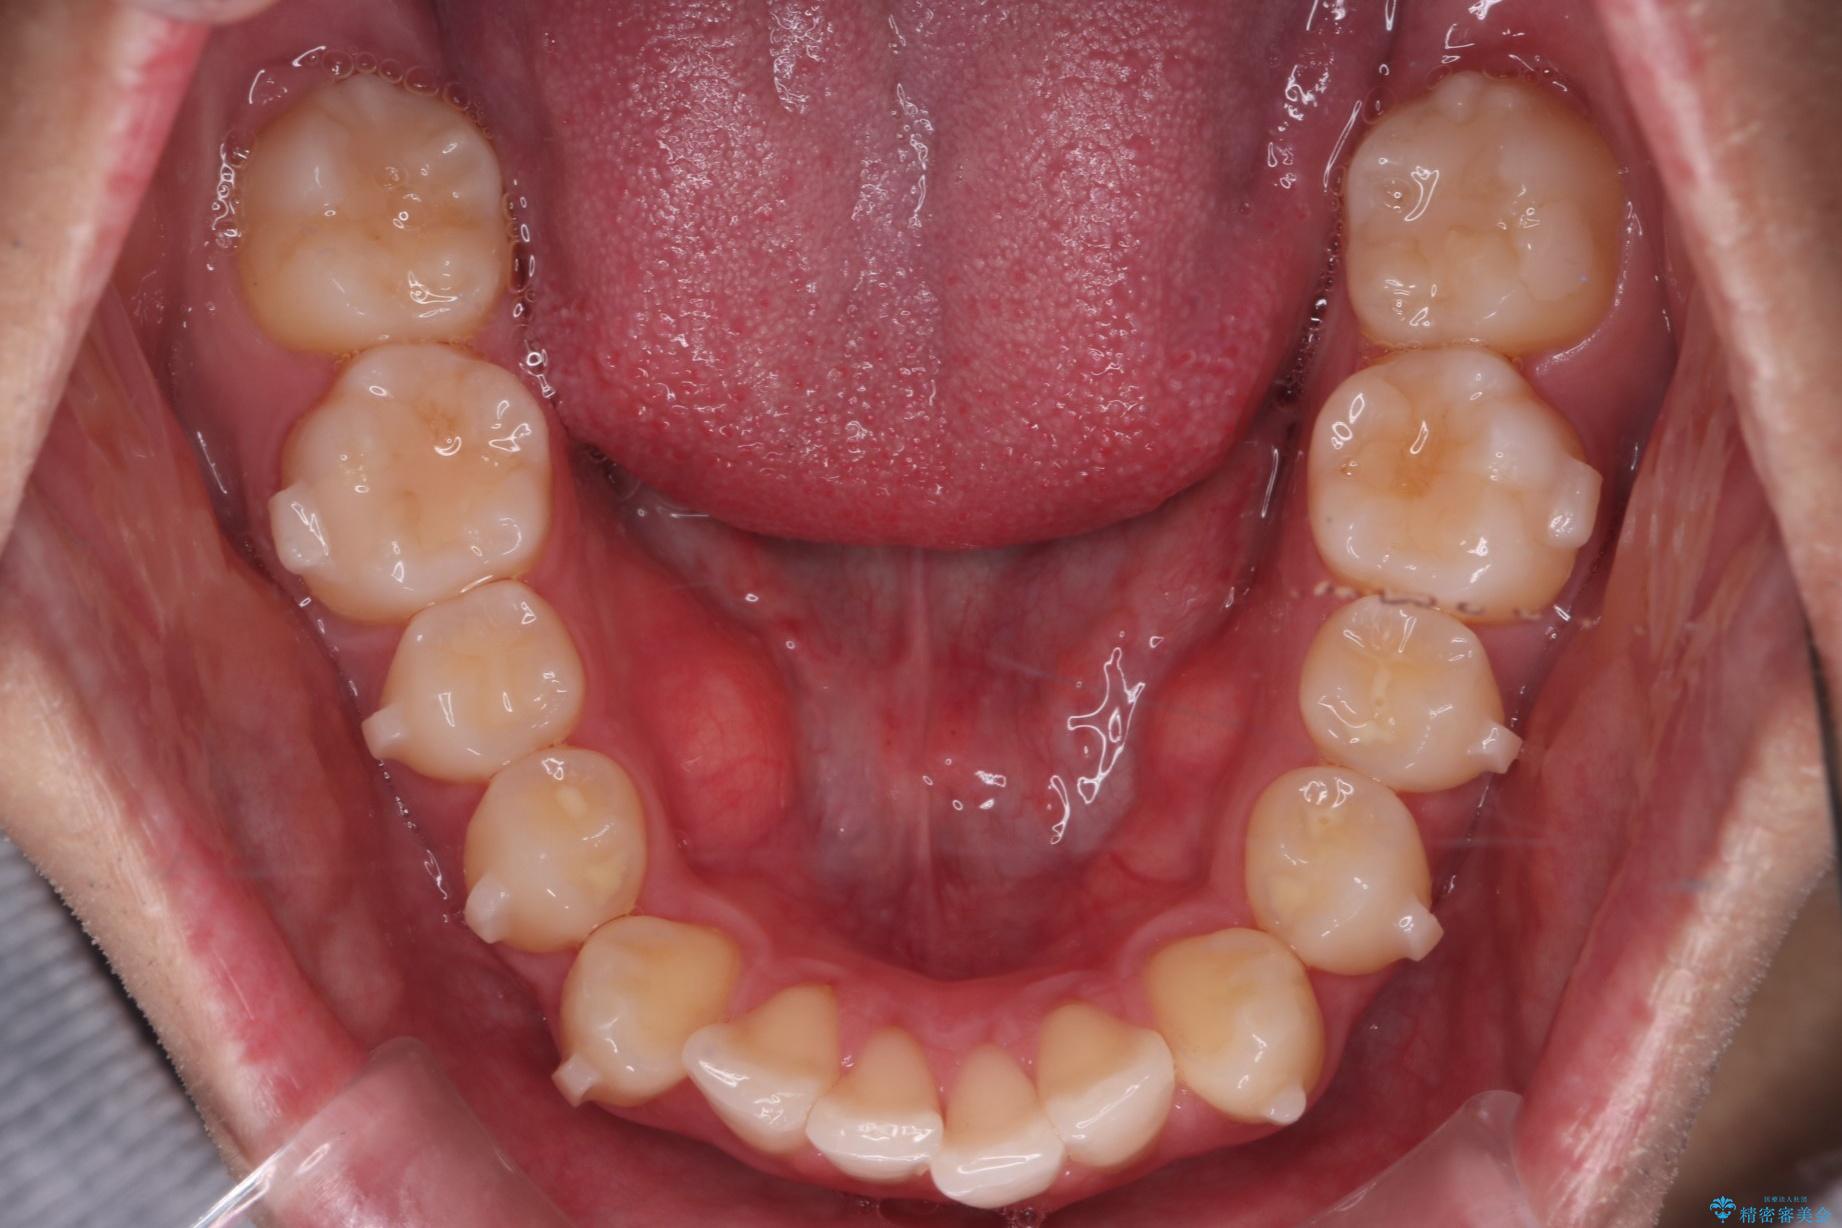

上の前歯が出ているのが気になるとご来院された患者様です。

IPR(歯と歯の間を削る処置)を行うことで、前歯の位置とがたつき整える治療計画を立てました。

患者様はシミュレーション通りに歯が動くのかと心配されていました。

可能な限り計画通りに歯を動かすために、マウスピース1枚あたりの使用時間を長めに使っていただきました。

そのため、多少治療期間が延びましたが、リファイメント(マウスピースの再発注)なしで終了することができました。